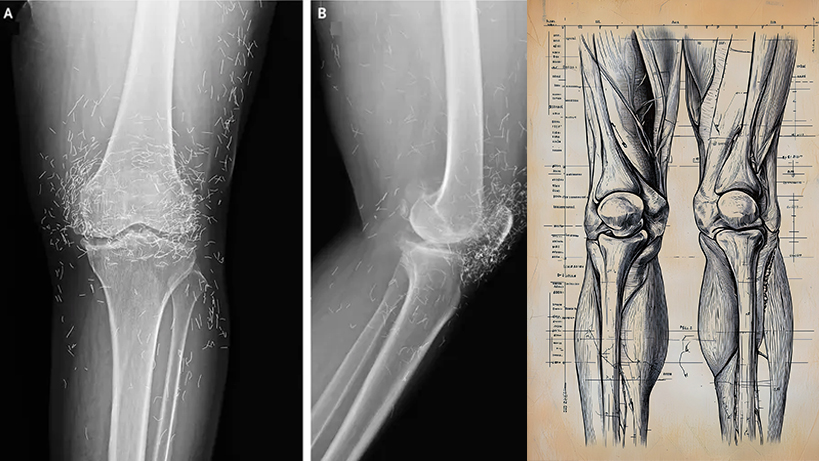

Daha sonra dizleri daha da çok ağrıdığı için hastaneye gitti. Sol dizinin röntgenleri, eklemin iç kısmındaki kaval kemiğinin kalınlaştığını ve sertleştiğini ortaya çıkardı. Ayrıca kaval kemiğinin iç kısımlarında ve diz ekleminin yanındaki uyluk kemiğinde mahmuz adı verilen kemik büyümeleri vardı.

Doktorlar ayrıca röntgende diz ekleminin etrafında yüzlerce benek gördü ve bunların küçük altın iplikler olduğu ortaya çıktı.

Doktorlar bu ipliklerin kadının akupunktur tedavisinin bir parçası olarak yerleştirildiğini öğrendi. Bu kısa, steril altın iplikler, sürekli stimülasyon sağlamak için dokuda kasıtlı olarak bırakılmıştı.

Doktorlar diz vakasıyla ilgili raporlarında, akupunktur sırasında yerleştirilen altın ipliklerin röntgen filmlerinin okunmasını zorlaştırabileceğini belirtmişlerdir.